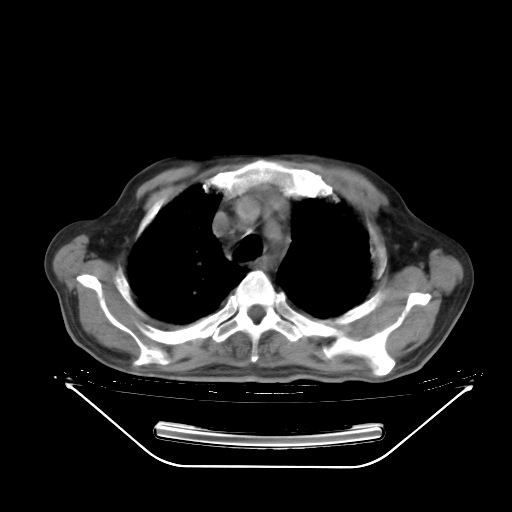

今天复查肺部CT,发现双肺广泛磨玻璃样改变。所以我把3月19日和5月9日相隔50天的肺部CT上传。请大家会诊。

5月9日肺部CT(在4月27日齐鲁医院肺部CT描述部分肺组织磨玻璃样改变,12天后肺组织广泛磨玻璃样改变)

2009年5月9日肺部CT